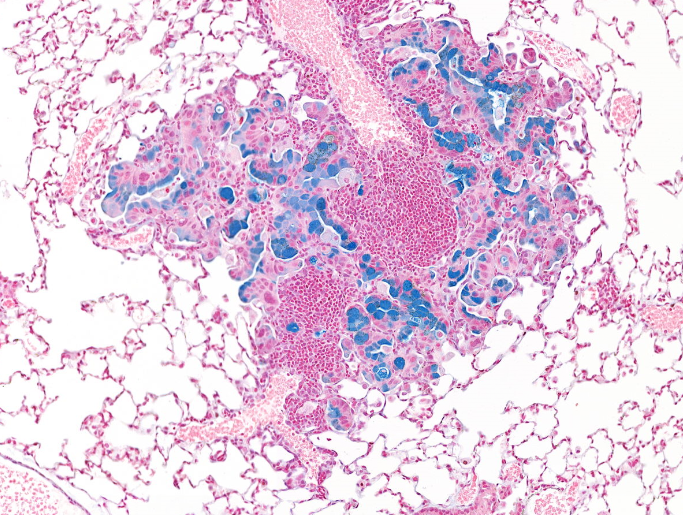

For my thesis research at Einstein, I joined the laboratory of Dr. Chandan Guha in the Department of Radiation Oncology to study how the physical characteristics of radiation can alter its biological effects. I investigated the impact of radiation energy on hematopoietic, gastrointestinal, and immunologic injury using orthovoltage X-rays and 137Cs γ-rays and identified an energy dependence of relative biological effectiveness (RBE) using modern preclinical irradiators. In collaboration with the New York Proton Center, I studied the effects of pencil beam scanned FLASH proton therapy on gastrointestinal toxicity. Furthermore, I have coordinated multi-institutional collaborations with the NASA Space Radiation Laboratory at Brookhaven National Laboratory and the Heidelberger Ionenstrahl Therapiezentrum to elucidate the immunologic consequences of carbon ion radiotherapy in pancreatic cancer. I am currently funded by an NCI Ruth L. Kirschstein National Research Service Award (F30CA278322).